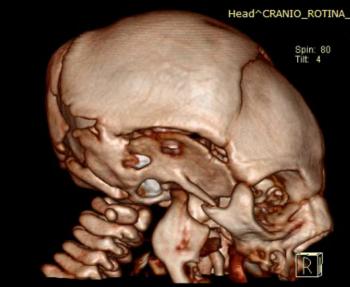

The first study looks at CT findings of the central nervous system in 16 newborn babies with congenital Zika virus infection confirmed by tests in cerebral spinal fluid.

The researchers identified a pattern of CT brain findings in the babies, including decreased brain volume, simplified gyral pattern, calcifications, ventricular dilatation and prominent occipital bone.

"We live in Pernambuco, a state in northeastern Brazil, which had the highest number of patients with microcephaly during the Zika outbreak in our country," said study author Natacha Calheiros de Lima Petribu, M.D., from the Department of Radiology at Barão de Lucena Hospital. "Our study proves that Zika virus infection can cause congenital brain damage in babies with and without microcephaly."